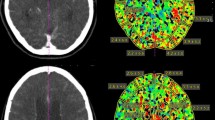

Normalization of MCA Territory and Longitudinal Observation

We assumed that vasospasm dominantly affect one MCA territory, which leads to interference within the regional examination areas of the left and right hemispheres. To investigate the extent to which perfusion measurements are influenced by this circumstance, we analyzed the ratios of left-to-right TTP values. In patients with DIND, we detected a significant change between left-to-right TTP ratios, particularly at the critical time frame between days 7–12. Patients with DIND showed a significant, 4.86 times increase of the left/right TTP ratio compared to a mean fold change in patients without DIND of 0.9 times (p = 0.032, Figs. 4a, 5).

Comparison between left-to-right ratios of TTP values between patients who present a delayed ischemic neurologic deficit and those who do not (a). b Longitudinal analysis of TTP values between these two groups. Patients with a delayed ischemic neurologic deficit (red) show a significant increase of left-to-right ratios, especially between days 10 and 12. TTP, time to peak

Illustration of left-to-right TTP ratios of all evaluated ultrasound perfusion examinations. Patients who present a delayed ischemic neurologic deficit are marked in red and those who presented without a delayed ischemic neurologic deficit are marked in green. Patients with delayed ischemic neurology deficit show an increase in TTP ratios, especially during the critical time period (8–12 days). TTP, time to peak

Comparison Between CT Perfusion and UPI

In order to validate our data by the most broadly used imaging method to quantify cerebral perfusion, we compared CT perfusion at early (3 days) and late timepoints (8–12 days) with paired UPI measurements. Paired CT and UPI data were available for 16 patients with highly significant correlation between right and left midbrain regions (R 0.92, p < 0.001) confirming the accuracy of UPI-TTP measurements. From comparing the left-to-right ratio (p = 0.2) or longitudinal development of TTP changes, we did not observe significant differences in neither MTT nor TTP perfusion from CT imaging (Fig. 6).

TTP CT imaging (left vs. right) measurements (red, with vasospasm; green, without vasospasm), correlation, and p values are determined by Pearson correlation coefficient (a). b Comparison between TTP longitudinal UPI (in black) and CT imaging (orange). c Barplot of differences between the left-to-right ratio within UPI (left) and CT (right) with vasospasm and without vasospasm. CT, computed tomography, TTP, time to peak, UPI, ultrasound perfusion imaging

Results of UPI in Symptomatic Patients

On longitudinal measurements of the left–right difference (LRDiff) of TTP comparing patients with DIND (red) attributable to cerebral hypoperfusion with those without DIND (green), LRDiff shows a significantly increase in patients with a DIND, with a peak at days 10–12 (p = 0.032) (see Fig. 4b).

Even though there is a pronounced variance of UPI measurements of the cohort, the parameter LRDiff showed a robust differentiation between affected patients and nonaffected patients.